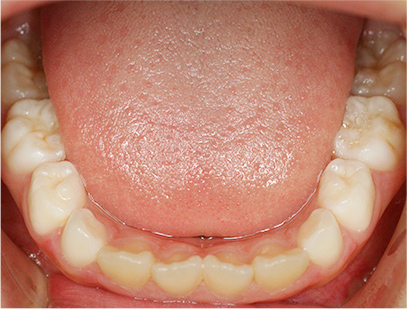

前歯部の開咬とデコボコ

前歯部が咬んでいないことを主訴として来院されました。精査、診断の結果「前歯部にデコボコを伴う開咬」と診断されました。

下の歯の裏側に舌が出ないように矯正装置を取り付け、そして上の歯には取り外しのできる矯正装置を装着して、側方に拡大を行います。

取り外しのできる矯正装置、舌が出せなくなる矯正装置(フェンス)